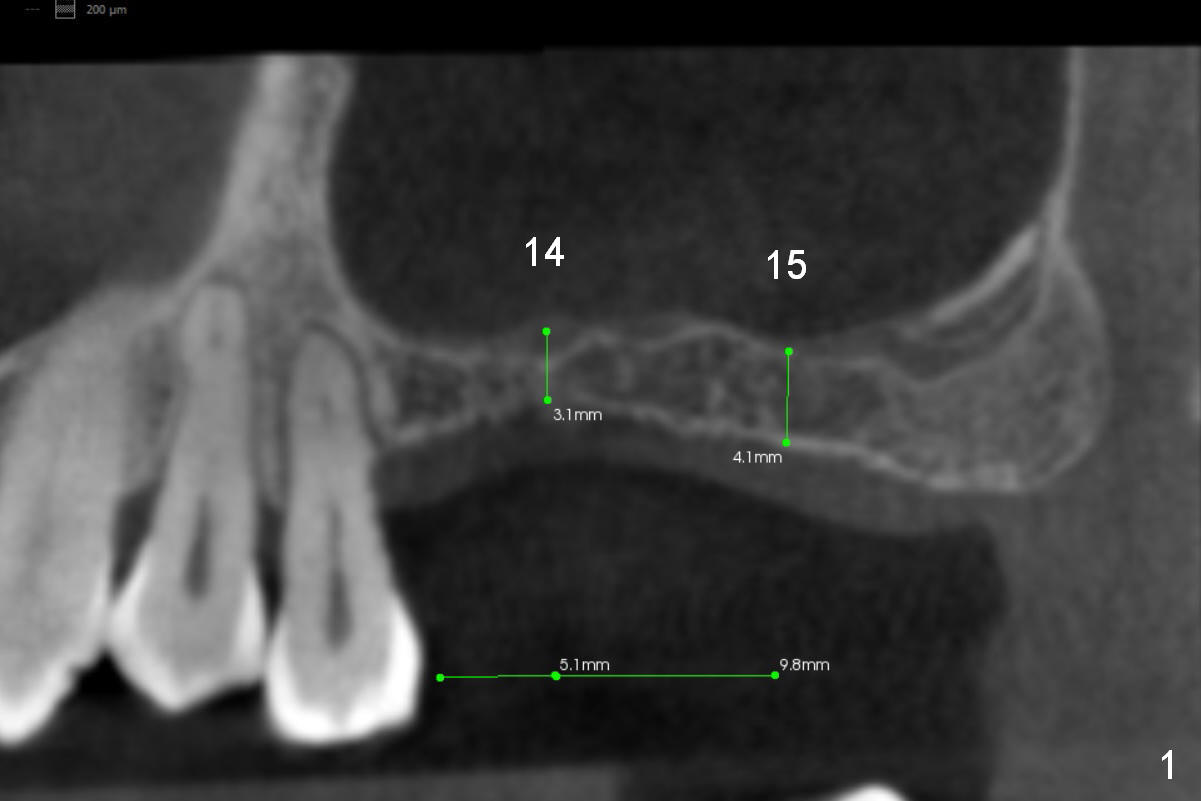

Although the patient agrees to have the tooth #13 with mobility II removed, implants at #14 and 15 should help alleviate occlusal trauma to the former. Initial osteotomy depth will be 1 and 2 mm at #14 and 15 (Fig.1: 1-2 mm from the sinus floor), followed Magic Sinus Lifter and bone graft. Implants to be placed are going to be 5x9 (at #15) or 5x7 (at #14) mm (Fig.2,3). Abutments (6x4(2) mm) will be placed if primary stability is achieved. Prepare torque wrench and the adaptor to measure torque value. Immediate splinted provisional is to be fabricated with occlusal reduction at #13.